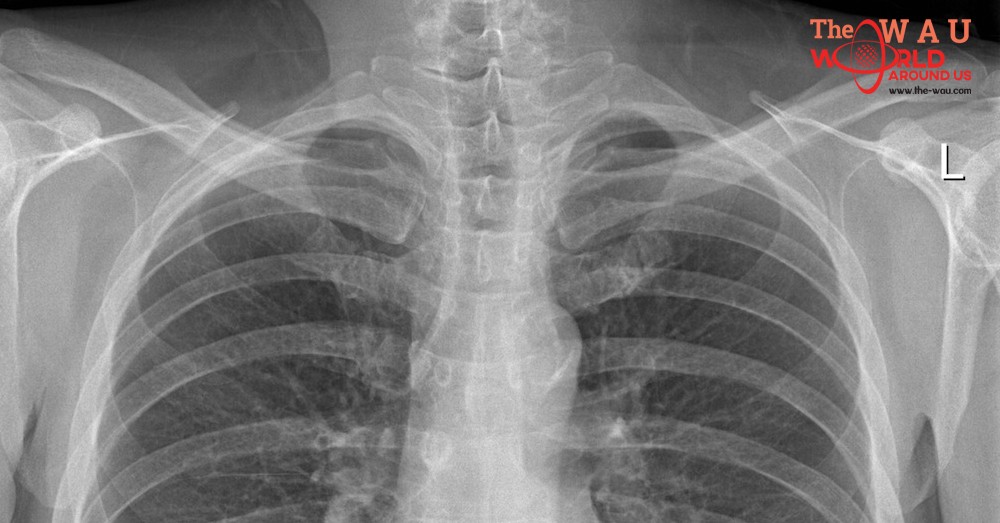

Oman’s Ministry of Health has said that a decision to introduce compulsory chest X-rays for all expats who renew their employment visas is to screen for tuberculosis (TB) in the country.

Before the new rule was implemented, expats were obliged to provide a chest X-ray on arrival, when receiving their first employment visa.

Speaking to Times of Oman, Dr Mohammed Al Yazidi, Director of Environmental and Occupational Health Department at the Ministry of Health, said: “This procedure has started to enhance the TB disease elimination strategy in Oman. Some people say that we are implementing procedures only for expats, or that this is a way of focusing on them. This is not true. The procedure is simply needed here because some expats come from countries where they might be exposed to the illness.”

Al Yazidi explained that the ministry uses various procedures to deal with patients, depending on the results of the X-ray scan, which include free treatment. However, expats who showed extremely critical cases of TB would face removal from the country.